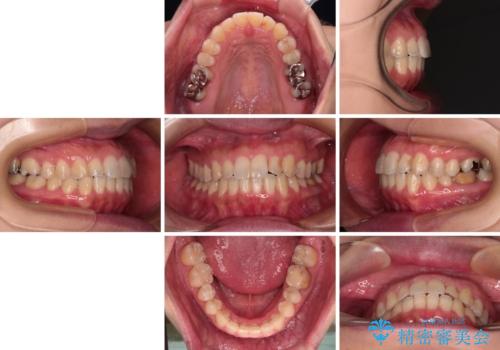

【モニター】上下前歯の叢生を解消 インビザライン矯正治療

- 前歯の捻れを気にして来院された患者様です。

上顎前歯が捻れて前方に飛び出しており、下顎前歯もそれに沿うようにデコボコとなっていました。

IPR(歯と歯の間を削る処置)によりスペースを獲得して上下前歯のデコボコを改善し、インビザラインにて矯正治療を行うこととしました。

捻れていた前歯の形態が、先端が欠けていたり、一部むし歯処置により左右非対称の形態となっていたため、なかなかゴールが定まらず、治療期間がかかってしまいました。